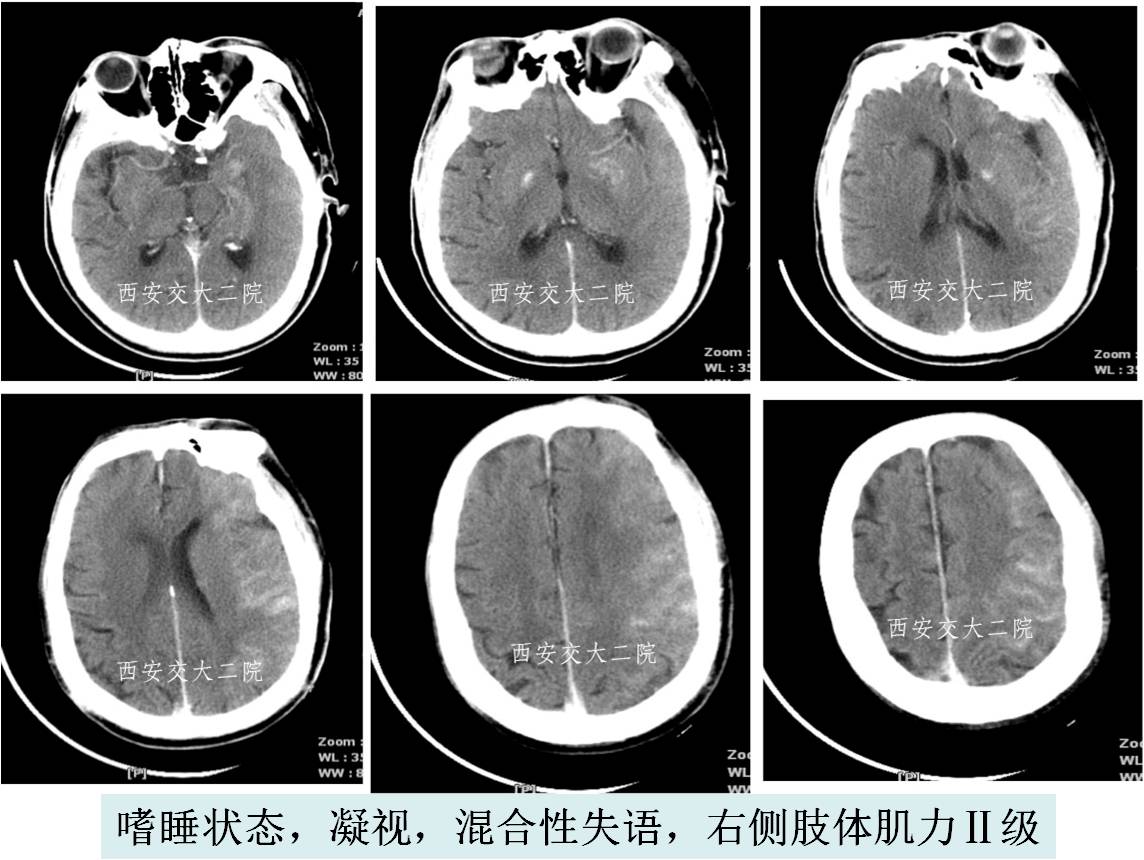

》查体:嗜睡,混合性失语,双眼向左凝视,双侧瞳孔形圆等大,直径约3mm,对光反射灵敏,右侧肢体肌力0级。

急诊脑CT

取栓后即刻脑CT及临表

术后24h脑CT及临表

术后4天脑CT及临表

术后2周脑CT及临表